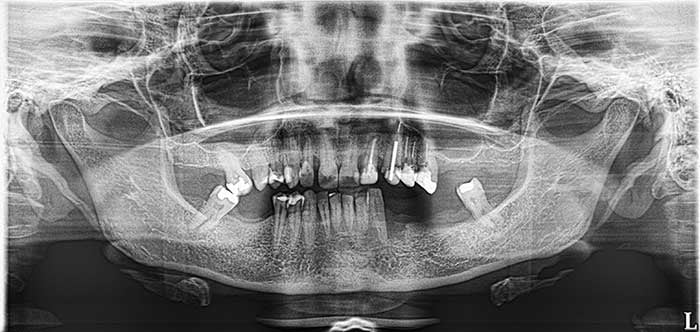

Our Work

Smile Gallery